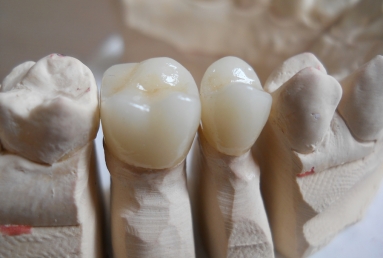

Full ceramic crowns on upper second premolar and first upper molar